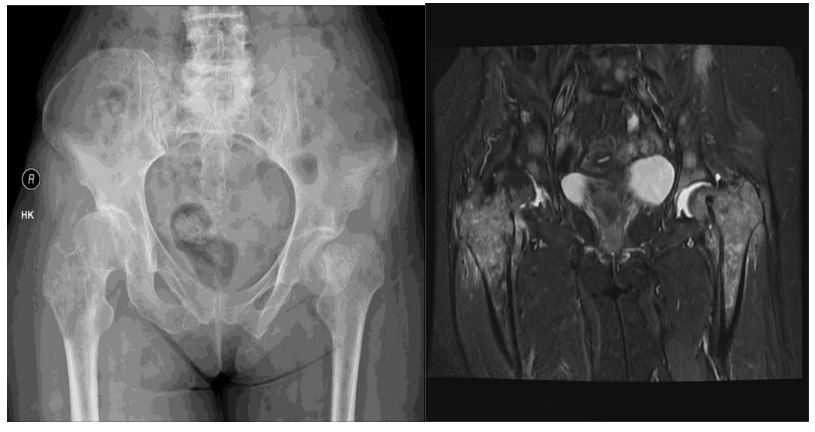

CASE 29: Risk of fracture in the right hip due to breast cancer metastasis, fracture in the left hip.

Before the surgery: X-rays and MRIs show extensive metastasis causing damage to the upper part of the right femur and a fracture in the left hip.